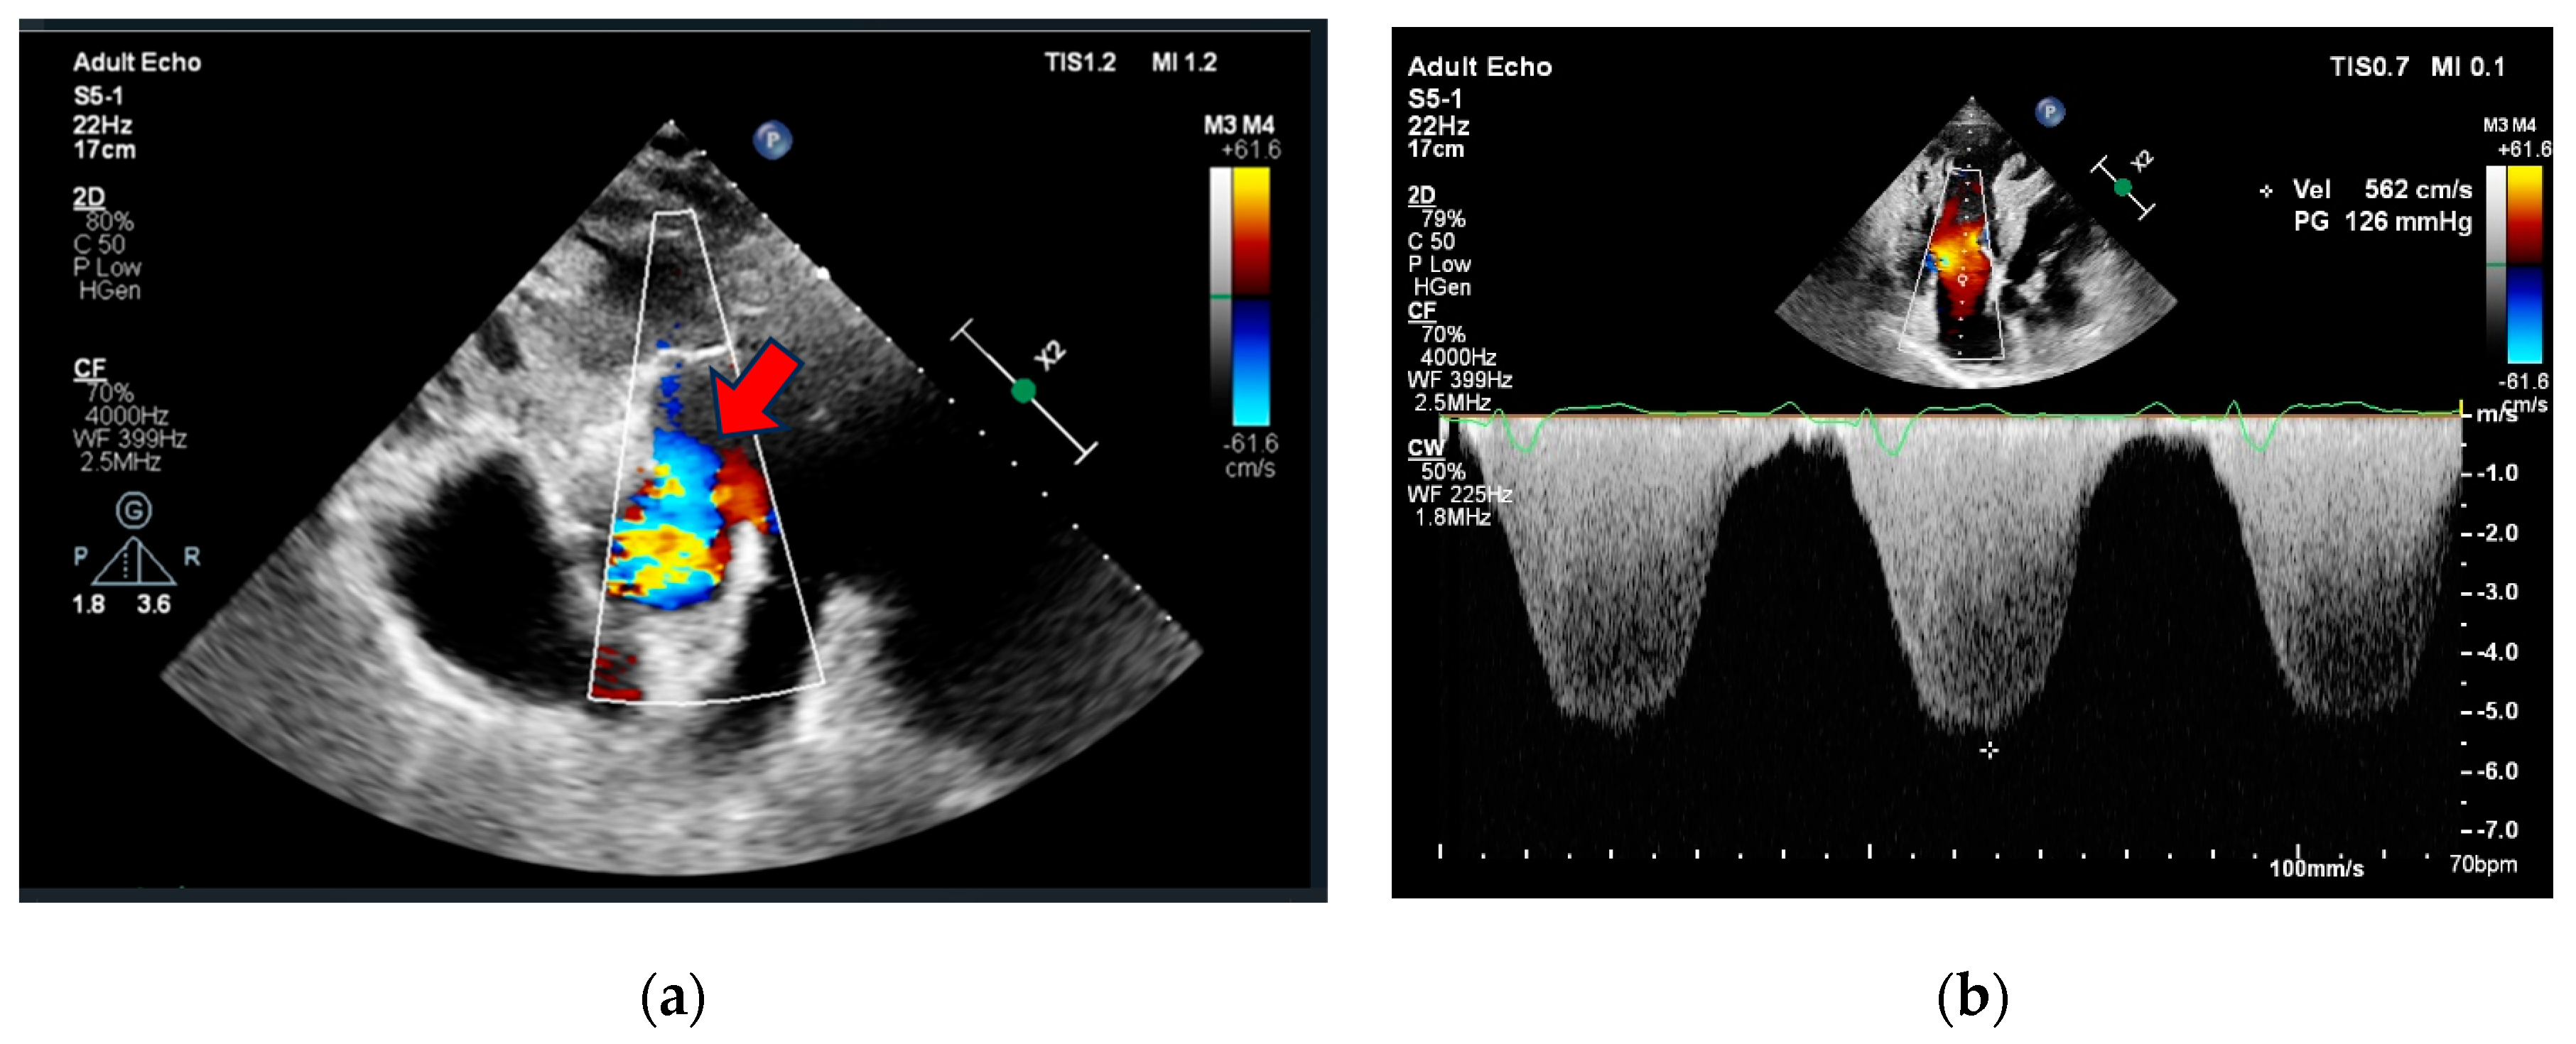

Initial investigations included an electrocardiogram (ECG), laboratory tests (biochemistry, D-dimer, Troponine I and B-Type Natriuretic Peptide levels), chest X-ray, and echocardiography. The case was discussed with pulmonologists at the PH center. Due to the deteriorating condition of the patient (increased dyspnea, elevated BNP levels, RV overload signs in ECG with no dynamic ST-segment and T-wave changes compared to previous ECG, reduced RV function, RV overload, and severe PH signs, preserved LV function without regional wall contraction abnormalities in echocardiography), a new PE episode could not be excluded. Initial clinical data are provided in Table 1 and Figure 1 and Figure 2. The patient was subsequently hospitalized in the pulmonology clinic for further investigation and treatment correction.

Figure 2. Echocardiography (a) parasternal short axis view showing aortopulmonic window (red arrow), (b) apical 4-chamber view showing right ventricle dilatation, hypertrophy, severe tricuspid regurgitation, and pulmonary hypertension.